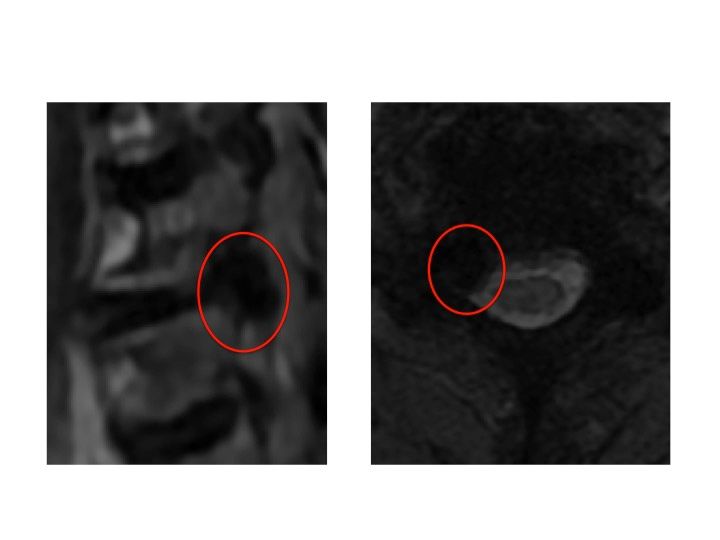

Nelle foto si può vedere un intervento di asportazione di ernia cervicale che ha causato nella paziente una perdita di forza della mano fortemente debilitante. L'intervento è stato eseguito presso il centro chirurgico toscano in convenzione con il sistema sanitario nazionale. La paziente sta gradualmente migliorando anche grazie alla fisioterapia. La scelta di un intervento chirurgico equivale ad intraprendere di un percorso che inizia dalla prima visita ambulatoriale e che prosegue con i successivi follow up. Lungo questo percorso il chirurgo e il paziente camminano insieme affrontando le stancanti salite e le successive discese per raggiungere gli obiettivi fissati nel primo incontro.